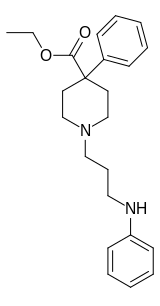

4-Phenylpiperidines

Pethidines (meperidines)

Structures